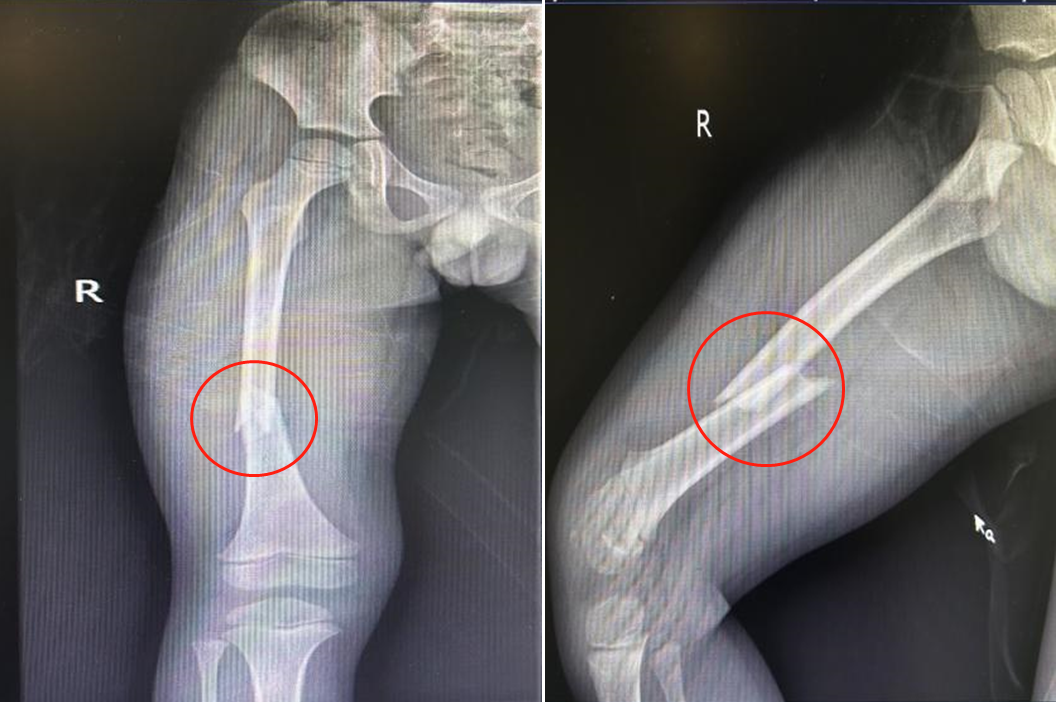

一周前,小江因车祸受伤倒地,受伤后右大腿疼痛、肿胀、畸形、活动障碍,X线检查,提示为右股骨中上段骨折。

患儿骨折移位明显,如果采用手法复位石膏外固定困难重重,患儿需要忍受疼痛、且失败风险极高。考虑患儿还比较小,传统切开复位钢板内固定虽可解决问题,但遗留伤口较大。杨开波主任组织骨一科专家团队一起讨论研究,综合考虑患儿年龄、骨折部位、骨折类型等因素,为了孩子能够更快更好地康复,尽量减少后遗症,决定行技术难度大、但预后效果好的“闭合复位、弹性髓内钉内固定术”。